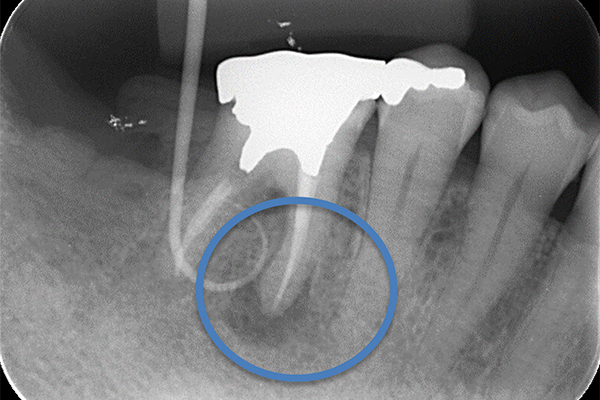

根の横に誤った穴をあけてしまい、気づかずに薬を入れてしまっている。また、器具が破折し、根の先に飛び出ている。

※本来の根管に薬が入ってることがわかります。